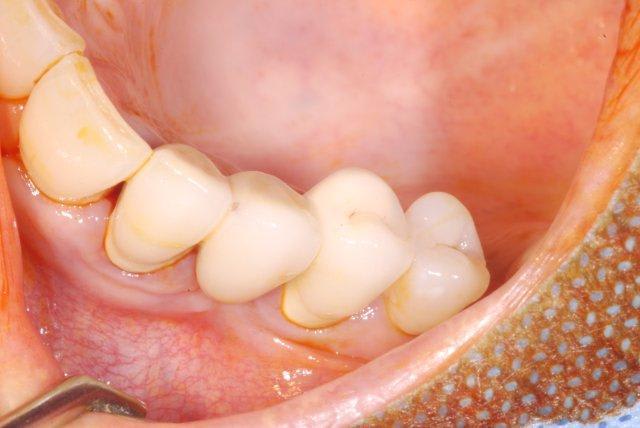

résultat à j+5

c'est pas si mal, le "greffon" est rose et ne semble pas s'être nécrosé.

attendons encore 3 mois..